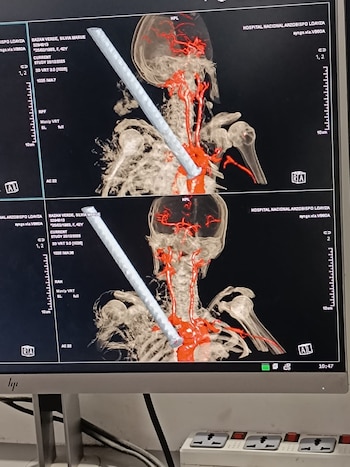

Médicos del Hospital Nacional Arzobispo Loayza (HNAL), en Lima, lograron retirar un fierro de construcción incrustado en el tórax de una mujer de 42 años, tras una intervención quirúrgica de alta complejidad. El objeto metálico atravesaba la región supraclavicular derecha, a escasa distancia del cayado de la aorta, representando un riesgo extremo para la vida de la paciente. Actualmente, permanece bajo monitoreo en la Unidad de Cuidados Especiales, estable pero con pronóstico reservado debido a la gravedad de sus lesiones.

En el Hospital Nacional Arzobispo Loayza, la paciente ingresó a la Unidad de Shock Trauma y fue evaluada por especialistas en cirugía de tórax y cardiovascular. Se convocó a una junta médica que determinó la necesidad de una intervención quirúrgica urgente. La operación, que se realizó el 26 de diciembre, se extendió por varias horas y concluyó con la extracción exitosa de la barra metálica, ubicada peligrosamente cerca de grandes vasos sanguíneos.